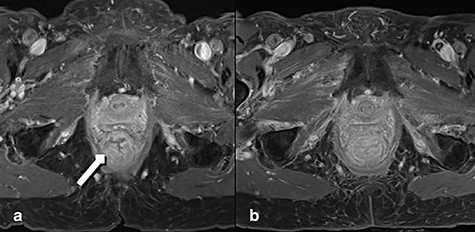

A 92-year-old woman, with known dementia and no previous history of anorectal surgery, was referred to the emergency department with a full-thickness rectal prolapse. Two months before she was diagnosed with advanced lower rectal cancer. Initially treated for hemorrhoids, a colonoscopy was arranged when patient noticed a resistance while introducing suppositories. Comorbidities were coronary heart disease and bronchial asthma. Family history was bland regarding tumor diseases. The colonoscopy demonstrated a malignant polyp of 4 cm size (3–4 cm above the anal verge). There was no clinical or endoscopic evidence of full-thickness rectal prolapse. The histology showed a moderately differentiated microsatellite-stable adenocarcinoma. A computed tomography and a magnetic resonance tomography (MRT) resulted in a cT3–T4 cN1 cM0, circumferential resection margin (CRM) positive (0 mm) staging (Fig. 1a). The multidisciplinary tumor board recommended an abdominoperineal resection. Despite detailed discussion with the patient and relatives a curative approach was declined, inter alia, because of age, comorbidities and dementia. Therefore, a palliative short-course radiotherapy with 5 × 5 Gy was performed [6].

MRT Imaging little pelvis. (a) Before radiotherapy. Tumor appears in the lower rectum with suspicion of muscle infiltration (long arrow). (b) Imaging after short-course radiotherapy.

Two weeks after the radiotherapy the patient noticed severe perianal pain. The patient’s relatives observed a painful partially reducible perineal bulge; thus, a rectal prolapse was diagnosed. At presentation in the emergency room the prolapsed segment of the rectum appeared edematous. The endoscopy showed a residual tumor completely included in the prolapsing rectum. MRT confirmed severe edema in the entire rectum after radiation and prolapse with poor definition of the tumor (Fig. 1b). The indication for perianal rectal prolapse resection was given and performed by Altemeier’s technique.